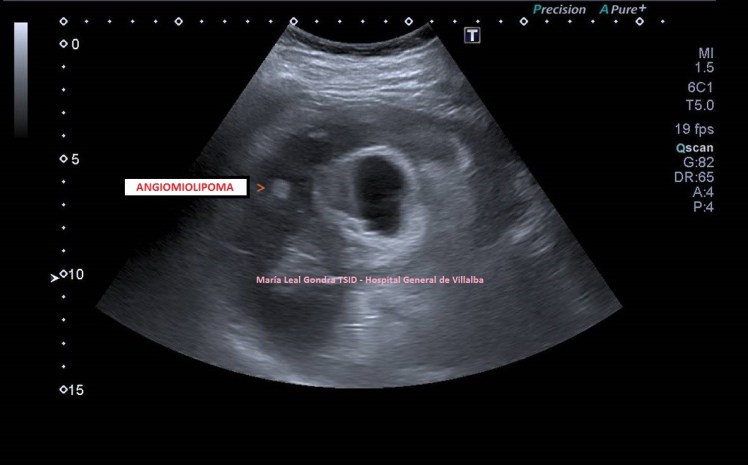

En el post de hoy, desde un oasis, vamos a ver varias imágenes, pero son importantes dos imágenes. De dos personas distintas. Con una lesión en una misma localización anatómica. Una benigna y la otra maligna.

El corte pertenece al polo superior del riñón derecho en el estudio de protocolo de ecografía de abdomen. La conseguimos haciendo este corte:

Este es el modo en el que vamos a colocar el transductor, es un corte longitudinal, donde vemos dibujada la anatomía ecográfica de la imagen 1, de superficial a profundo, piel y tejido celular subcutáneo, inapreciable, pared a abdominal y musculatura superficial, no dibujada, y luego órganos compactos, hígado, riñón derecho, entre ambos, le espacio de Morrison…más profundo el psoas iliaco. El riñón derecho dividido en corteza y seno renal, hipoecogénica e hiperecogénica respectivamente.

En la imagen 1 ves normalidad. La anatomía básica es vital, la semiología que nos habla de isoecogenicidad entre la corteza renal y el parénquima hepático cuando ambos están en situación de normalidad. Esto es básico en esta ecoarquitectura global donde conviven ambos órganos.

1

En la imagen 2 ves una lesión grande, redonda, de aspecto quístico, anecoica de bordes bien definidos y finos, con buena transmisión de sonido.

2

En la imagen 3,4 y 5 ves una lesión en la misma localización, ecogénica, sólida, heterogénea, redonda y de gran tamaño, lobulada. Tiene vascularización y es heterogénea. Flecha amarilla.

Ambas lesiones ubicadas en el polo superior del riñón derecho. más profundo que el polo inferior, normal, desde el punto de vista ecográfico, según la disposición de la sonda y la situación espacial del riñón en la anatomía humana de modo general, siempre a expensas de rotaciones y variantes de la normalidad.

3

4

5

La semiología nos sirve para identificar lesiones, que la radióloga pueda discernir si éstas, por su aspecto ecográfico, son o no son compatibles con malignidad y en este caso ampliar el estudio si lo considerase oportuno con CT o RMN.

Nos quedamos con la imagen 3 y 4, y en este caso observamos que es una lesión que la paciente ya tenía años atrás y que fue objetivada ecográficamente, de menor tamaño y que en tres años ha crecido considerablemente y que no ha sido tratada durante este tiempo por motivos que desconozco.